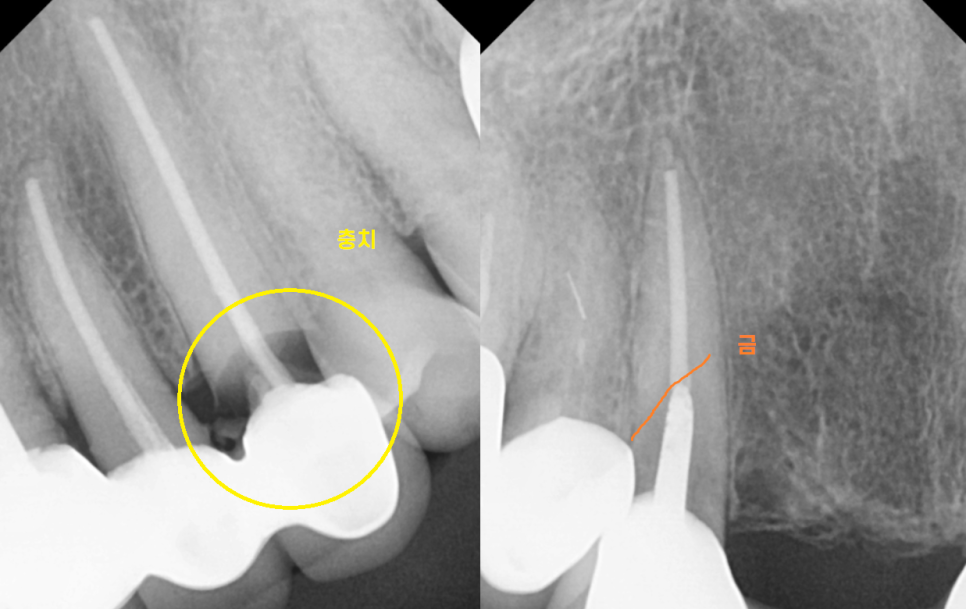

충치가 많이 먹은 송곳니

기둥까지 넣어 보강한 치아의 실금

양쪽 송곳니 두개 다 문제가 있었습니다.

브릿지는 할 때는 편안한데

문제가 생기면 치료하기가 아주 까다롭습니다.

일단 묶어둔 6개의 치아를 모두 벗겨내야하고

걸어둔 치아가 문제가 생기면

그 옆에 치아를 깎아야하는데

그 옆에 치아가 상태가 별로다?

임플란트다?

그럼 브릿지 치료가 어려워지거든요~

결국 문제가 되는 치아들을 발치 후

앞니 브릿지 교체를 진행하기로 상담해드렸습니다.

앞니는 잇몸과 뼈가 얇아서

임플란트를 심을 공간이 안나올 때가 많습니다.

단순히 공간만 안나오는게 아니고

임플란트와 뼈가 잘 안붙을 수도 있는 문제다보니ㅠㅠ